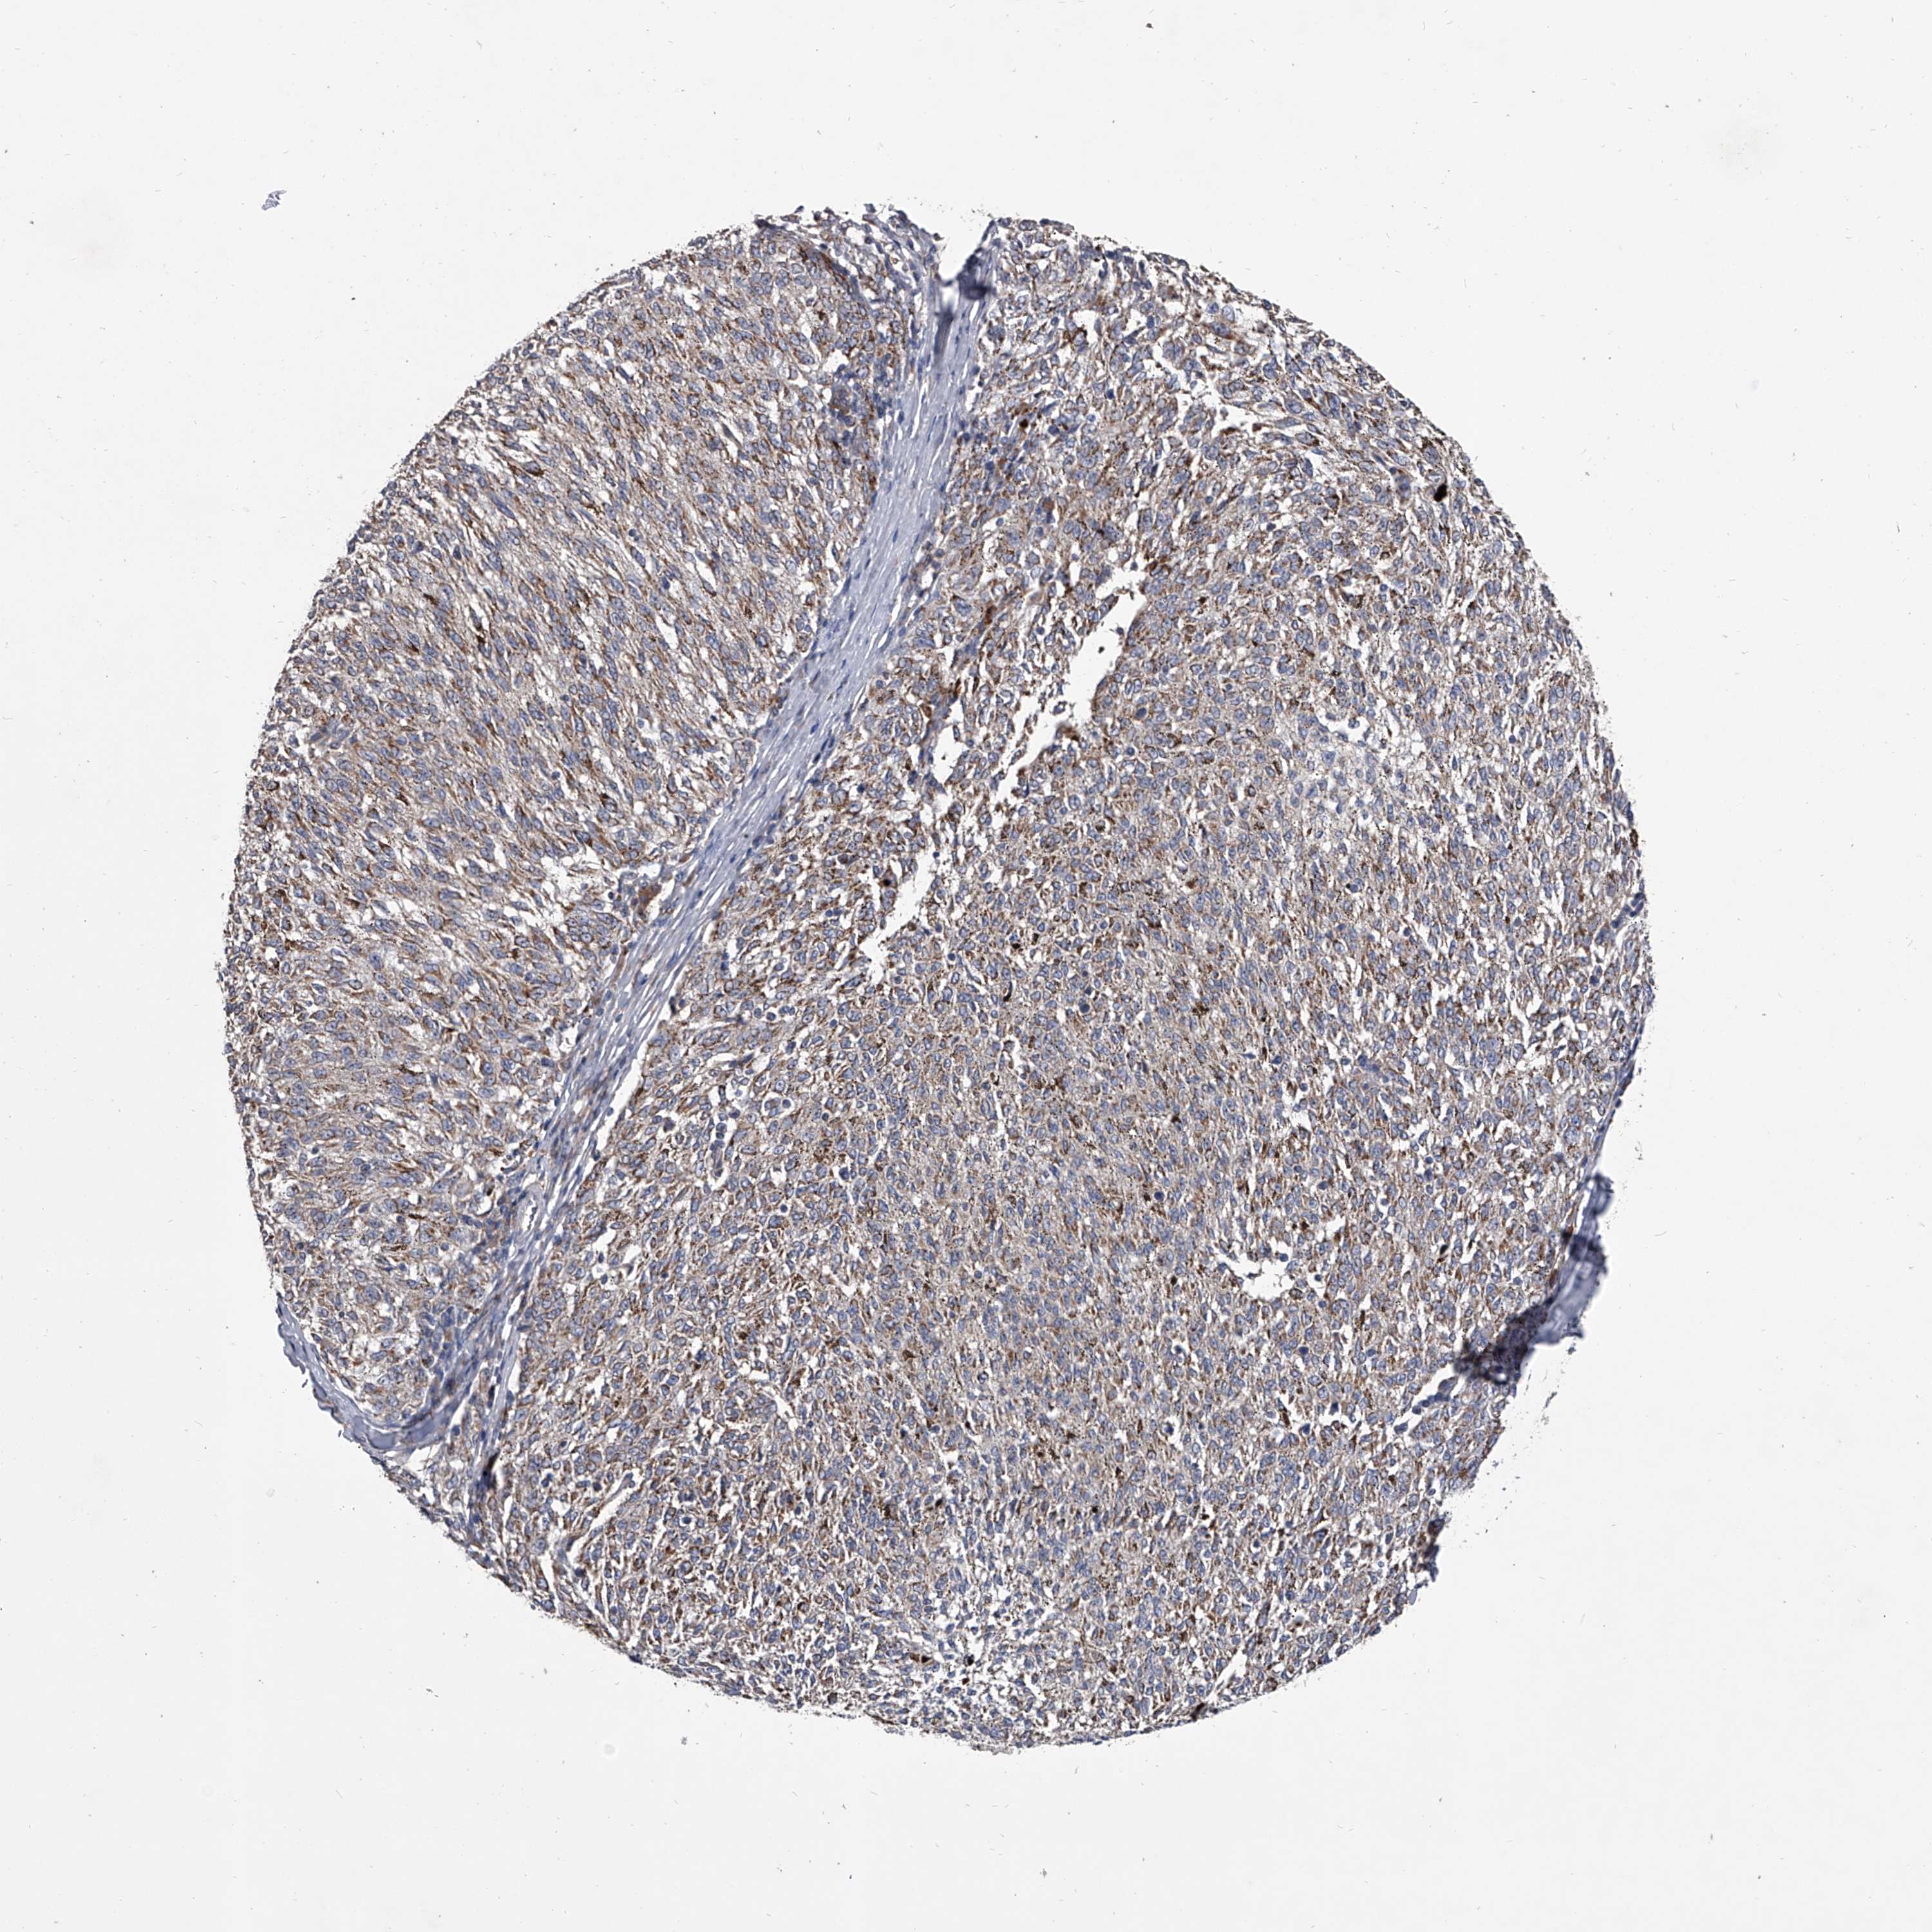

MELANOMA - Protein expressioni

A mouse-over function shows sample information and annotation data. Click on an image to view it in a full screen mode. Samples can be filtered based on level of antibody staining by selecting one or several of the following categories: high, medium, low and not detected. The assay and annotation is described here.

Note that samples used for immunohistochemistry by the Human Protein Atlas do not correspond to samples in the TCGA dataset.

Antibody stainingi

Antibody staining in the annotated cell types in the current human tissue is reported as not detected, low, medium, or high, based on conventional immunohistochemistry profiling in selected tissues. This score is based on the combination of the staining intensity and fraction of stained cells.

Each image is clickable and will lead to virtual microscopy that enables deeper exploration of all samples and also displays staining intensity scores, fraction scores and subcellular localization as well as patient and tissue information for each sample.

Antibody HPA030278

Antibody CAB004511

Staining

High

Medium

Low

Not detected

Intensity

Strong

Moderate

Weak

Negative

Quantity

>75%

75%-25%

<25%

None

Location

Nuclear

Cytoplasmic/membranous

Cytoplasmic/membranous,nuclear

Malignant melanoma, NOS

Malignant melanoma, Metastatic site